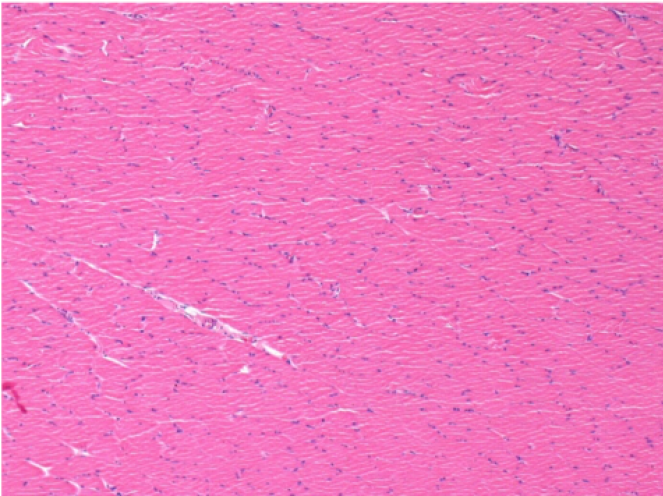

7 місяців (210 днів) після ін'єкції 0,1 мл Ендопіл в правий претибіальний м'яз.

Повна Restitutio ad integrum через 7 місяців

Л :Контроль 50x210 днів

П:50X-210 днів